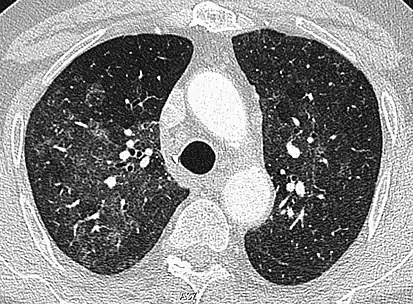

CT image in patient with COVID-19 showing bilateral ground-glass opacities at the periphery of both lungs.

Ground-glass opacity is among the most common imaging findings in patients with confirmed COVID-19.[16][17] One systematic review found that among patients with COVID-19 and abnormal lung findings on CT, greater than 80% had GGOs, with greater than 50% having mixed GGOs and consolidation.[16] GGOs with mixed consolidation has most often been found in elderly populations.[18] Several studies have described a pattern among initial, intermediate, and hospital discharge imaging findings in the disease course of COVID-19. Most commonly, initial CT imaging reveals bilateral GGOs at the periphery of the lungs. During initial stages, this is most often found in the lower lobes, although involvement of the upper lobes and right middle lobe has also been reported early in the disease course.[16][18] This is in contrast to the two similar coronaviruses, SARS and MERS, which more commonly involve only one lung on initial imaging.[19][20] As the COVID-19 infection progresses, GGOs typically become more diffuse and often progress to consolidation.[11][18] This is sometimes accompanied by the development of a crazy paving pattern and interlobular septal thickening.[18] In many cases the most severe pulmonary CT abnormalities occurred within 2 weeks after symptoms began.[17] At this point, many individuals begin showing resolution of consolidation and GGOs as symptoms improve. However, some patients have worsening symptoms and imaging findings, with further increase in septal thickening, GGOs, and consolidation. These patients may develop lung "white-out" with progression to acute respiratory distress syndrome (ARDS) requiring treatment escalation.[17][21]